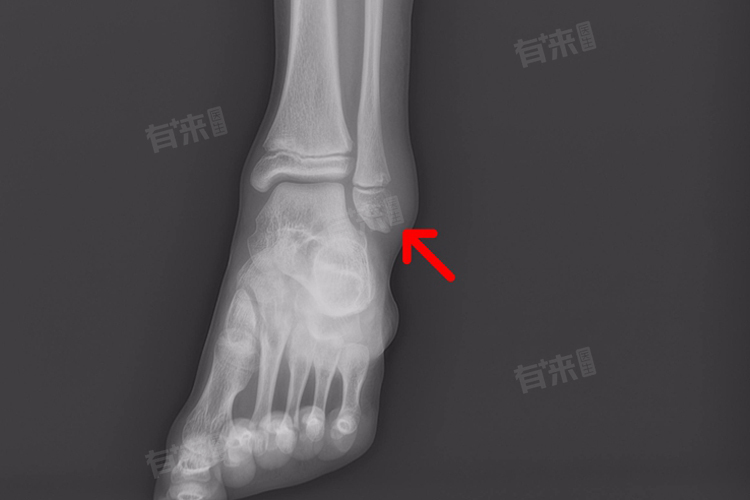

- 单纯性骨折:对于单纯性的脚外踝骨折,即骨折端移位程度较轻的骨折,通过手法复位石膏外固定或夹板外固定,患者通常会在6-8周达到临床愈合。此时,拍摄X光片可以发现骨折线已经模糊或消失,骨折端已经相对稳定,患者可以开始逐渐进行康复锻炼。

- 粉碎性骨折:对于粉碎性的脚外踝骨折,由于骨折端移位明显,通常需要手术治疗,如切开复位钢板螺钉内固定。术后,患者需要更长的恢复时间,一般8-10周骨折可以达到临床愈合。同样,此时也需要拍摄X光片来确认骨折的愈合情况。